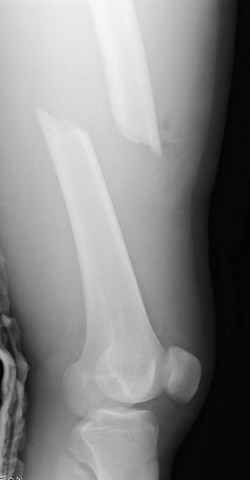

03.14.2005

больному 42, автоавария, политравма, открытая черепномозговая травма, безсознании, открытый перелом бедра, размозжение мягких тканей, дефект кожи на передней поверхности бедра около 13 см2 от ожога, компартмент синдром.

По поводу открытого перелома больной ургентно взят на ретроградное интрамедулярное штифтование, после рутинного дебрайдмента и фасциотомии на бедре и на голени.

перелом бедра

постоперационные